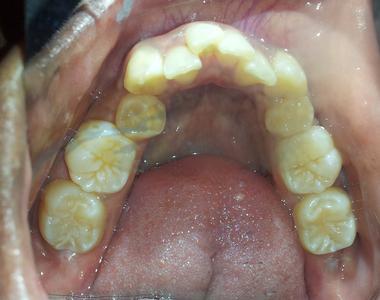

Dental Braces Smile Transformation: Patient Case Study